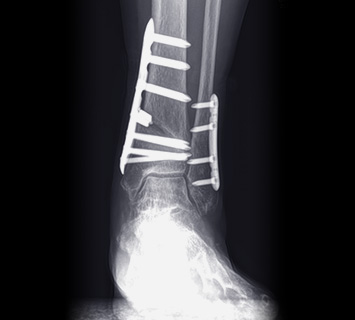

발목교정술

발목고정술

인공관절 수술